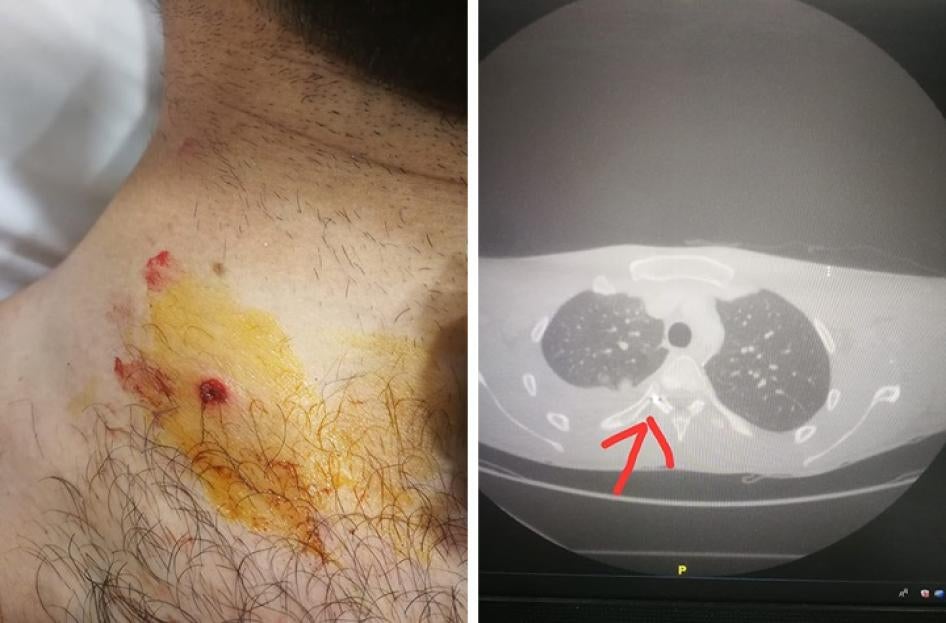

Karl Freiha, a nurse who was volunteering with the Secours Populaire Libanais to provide first aid to protesters, said a security member wearing a green camouflage Lebanese army uniform shot metal pellets at him from a distance of less than 10 meters while he was tending to an injured protester in the alley next to Dunkin’ Donuts, where the Virgin Megastore was formerly located.

“I was wearing a helmet, our vest, our pants, our medical backpacks,” Freiha said. “We were moving together, in a group, all in uniform. It was clear that we were medics.” Several metal pellets embedded in his skin, including in his buttocks and behind his knees. One pellet punctured his skin and lodged near his right rib, and another embedded in his scalp, next to his ear. “I felt like I couldn’t breathe anymore,” he said.

The same doctor treated another protester who was shot with a metal pellet in the neck. The doctor said that the pellet tore an artery in the neck, punctured the lung, and finally lodged in the protester’s spinal cord. The doctor said that, had the pellet been one millimeter closer to his spinal cord, the protester would have been permanently paralyzed.